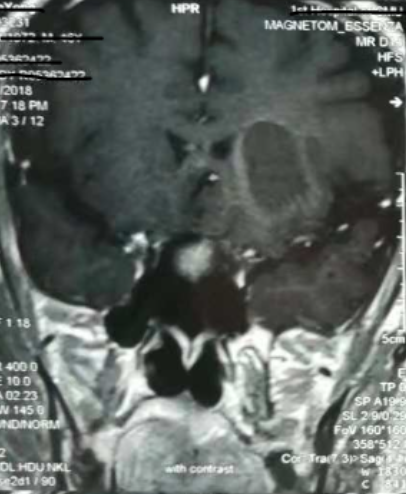

增強核磁提示:血腫液化周邊增強

手術日當天,醫(yī)生團隊通過手術計劃系統(tǒng)為患者制定手術靶點及最安全的入顱路徑,隨后將手術規(guī)劃導入手術室的機器人當中。